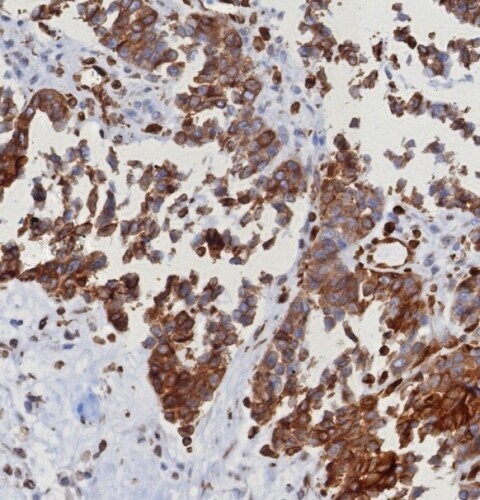

Supportive validation

- Submitted by

- Invitrogen Antibodies (provider)

- Main image

- Experimental details

- Formalin-fixed, paraffin-embedded human serous ovarian carcinoma stained with STING1 Recombinant Rabbit Monoclonal Antibody (STING1/8187R). HIER: Tris/EDTA, pH9.0, 45 min. 2 °: HRP-polymer, 30 min. DAB, 5 min.